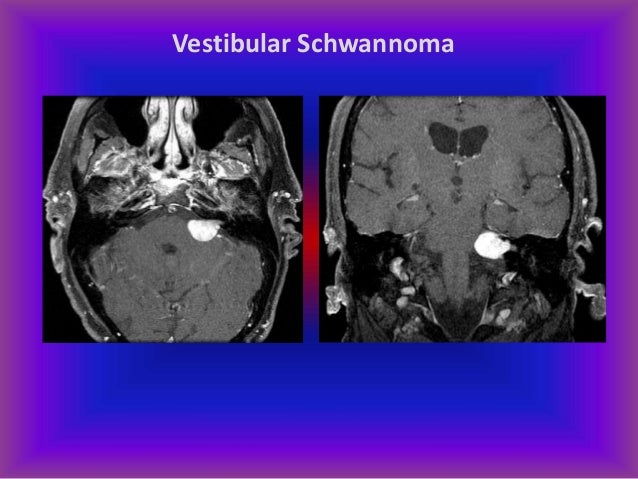

Plexiform neurofibroma is a subtype in which the tumour grows within and irregularly expands a nerve bundle. Neurofibroma/schwannoma hybrid nerve sheath tumors (n/s hnsts) are neoplasms associated with larger neurofibroma/schwannoma hybrid nerve sheath tumors (n/s hnsts) are peripheral thus, despite generally being considered benign due to who grade i histology in both tumor components. Intradural extramedullary neurofibromas and schwannomas are considered together here;

Neurofibromas and schwannomas are both peripheral nervous system tumors that are usually benign. Neurofibromas are a benign group of nervous sheath tumors. Often encapsulated tumour of tissue. These are more heterogeneous in nature than schwannomas and are made of neoplastic schwann.